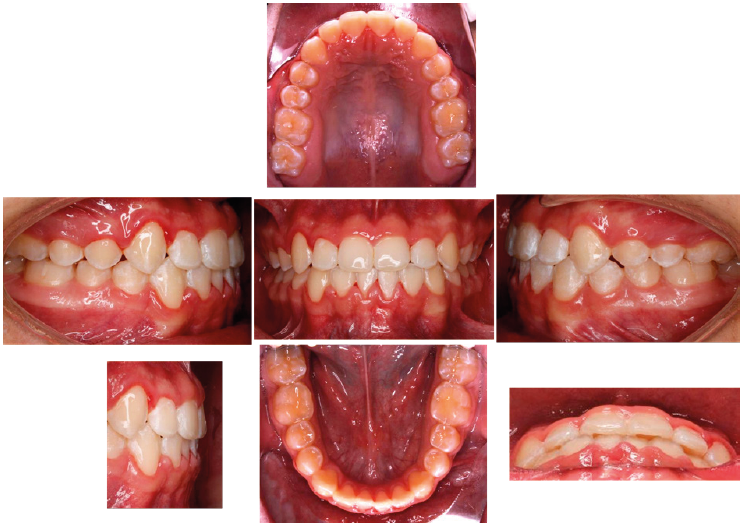

Se cerraron espacios tras la mesialización de caninos, primeros premolares y segundos premolares. Se colocó ligadura en bloque de 5-5 con e-link de 7-7 para cerrar espacios entre molares. Se colocaron arcos braided 0.021”x 0.025” superior y 0.019”x 0.025” inferior, y elásticos de asentamiento de 6 oz. Posteriormente se llevó a cabo un ajuste oclusal y se procedió al retiro de la aparatología fija (Figura 6) donde se observan los resultados finales y se confirmaron con los estudios de imagen (Figura 7). Derivado de las características del paciente se decidió optar por un retenedor Prefinisher (Figura 8).

Los cambios obtenidos tanto clínico como radiográficos, se observaron de manera considerable y los resultados dentales y faciales fueron satisfactorios. Se logró obtener una adecuada relación maxilomandibular de Clase I molar y canina, adecuadas sobremordidas horizontal y vertical; corrigiendo la hipoplasia maxilar y proporcionando rotación a la mandíbula hacia abajo y hacia atrás, asimismo se corrigió la mordida cruzada anterior y se obtuvieron líneas medias coincidentes.